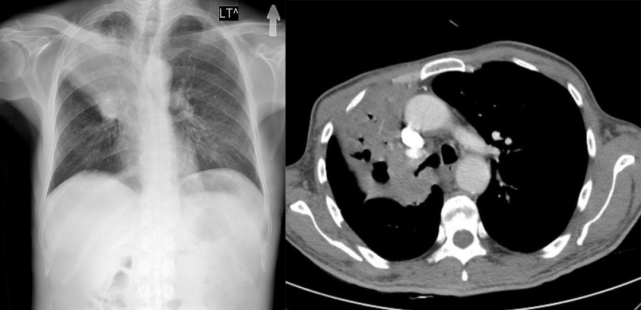

肺不张的诊断方法有哪些?

发现肺不张,先不要紧张不可过于担心,盲目地陷入肺癌恐慌,也不要妄下定论。

首先应该去找专科医生,医生还要通过问诊了解症状与病史,有必要的话还需做进一步检查,如血液学检查、影像学检查、支气管镜、剖胸检查等。

胸部 CT 可描述肺不张的位置与形状。支气管镜检查是肺不张最有价值的诊断手段之一,可进一步明确诊断肺不张的病因。

医生通过以上的检查结果来进行综合判断,明确诊断。一旦诊断明确,医生就会制定出相对应的有效的治疗方案。